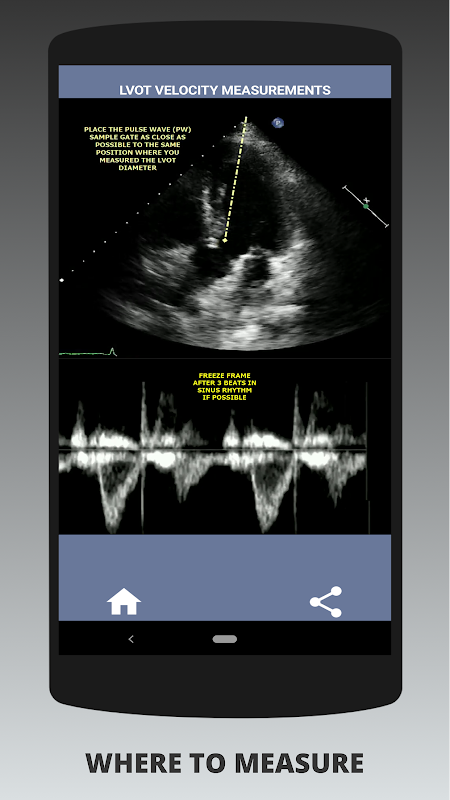

Wenn ein Befragter diese Fähigkeit stark nachweisen kann, hat er meiner Meinung nach einen großen Vorteil gegenüber den anderen Bewerbern, die in diesem Bereich schwach sind (das ist nur logisch, da es normalerweise so viele Fälle von Aortenklappenstenose gibt). Wenn Sie sich für eine Stelle als Herzsonograph bewerben, jemand, der nur seine Fähigkeiten auffrischen muss, oder ein Echo-Student, dann wurde diese App von einem derzeit praktizierenden Herzsonographen für Sie entwickelt. Einfach und kurz, auf den Punkt gebracht mit vielen anschaulichen Videos, die genau zeigen, wo genau gemessen werden muss (z. B. LVOT-Durchmesser) und wie gemäß den veröffentlichten ASE/ICAEL-Richtlinien gemessen wird.